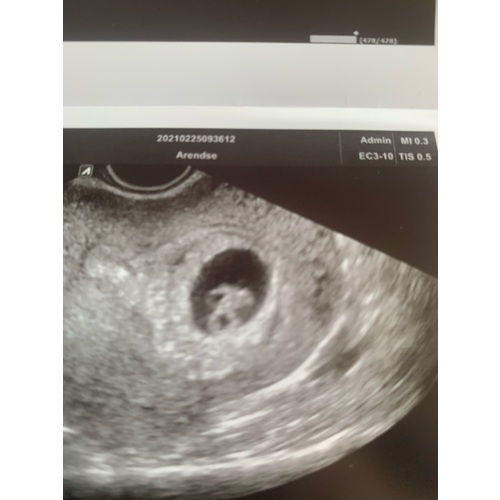

Bij mij is de echo inwendig genomen. Dan zou het volgens deze methode een meisje worden denk ik? Benieuwd wat de nipt als resultaat gaat geven ☺️

Inwendige echo: Zie je op de uitdraai van een inwendige echo de lichte vlek rechts in de baarmoeder? Dan verwacht je volgens de Ramzi-theorie een jongen. Wanneer je hem links in de baarmoeder ziet, zou je van een meisje in verwachting zijn.

Uitwendige echo: Als de echo via je buik is gemaakt, is de echo gespiegeld. Zie je op de uitdraai van de echo de lichte vlek rechts? Dan zou dit betekenen dat je een meisje krijgt. Een lichte vlek aan de linkerkant wijst bij een uitwendige echo op een jongen.

Kan iemand het bij mij zien? Deze is inwendig gemaakt.. ik zie zelf niet wa ...

Oke dan ben ik heel erg benieuwd wat dit dan eventueel kan zijn volgens de ramzi methode dit is een inwendige echo geweest bij 8 weken zwangerschap